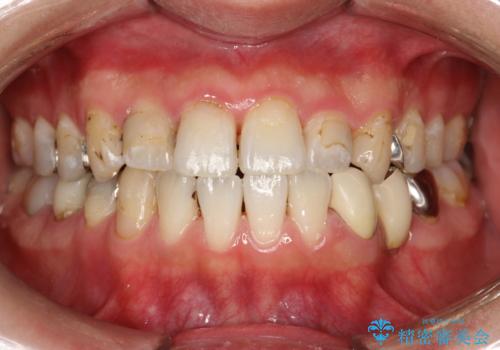

歯の表面に、茶色く色が残っている所がありますが、これは詰め物の変色の所と、虫歯になっている所です。以前に、CR(コンポジットレジン)による虫歯治療がされています。

CRは経年的劣化や、着色してしまうことがあります。PMTCでクリーニングを行うと、古いCRが目立つことがあるため、気になる際は詰め替えを行います。

茶色くなっている部分が、着色なのか、劣化なのか、虫歯によるものなのかは判別が難しいことがあります。そのため、定期的にPMTCを行うことで状態の確認が的確に行えます。

また、治療が開始される前などにも、全体的にクリーニングを行いご自身本来の歯の色、状態を精密に確認することが大切です。